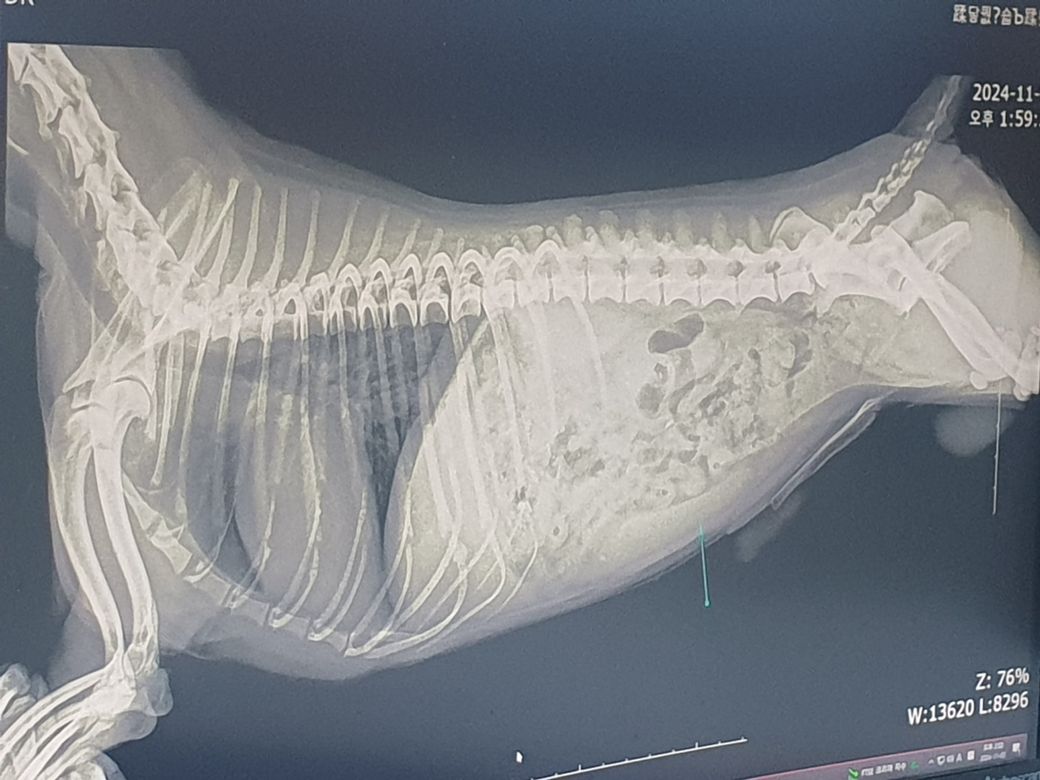

동물병원에 가서 X-ray 찍으니까(아래 사진) 다른곳은 이상이 없지만 비장이 크다고 적혈구에 문제가 생길수 있다고 말씀하시네요

항생제와 수액을 처방해주시고 구토와 설사를 동반하면 혈액검사를 해보자고 하시는데 구토와 설사 증상은 아직까지 없습니다. 제 강아지 괜찮을까요?